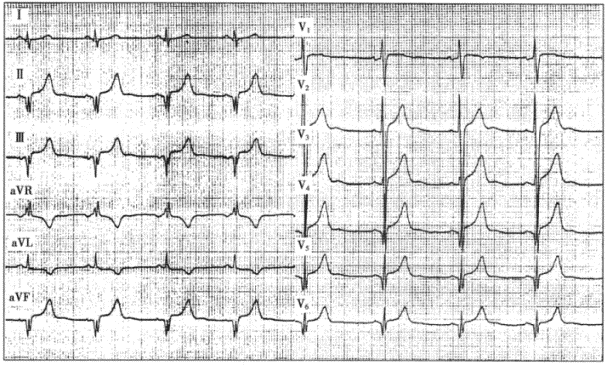

患者男性,25歲,因胸痛、氣短半年就診。血壓120/75mmHg,胸骨左緣3~4肋間聞及2/6級收縮期雜音。超聲心動圖提示室間隔厚度為20mm,左室后壁厚度為9mm,EF值為68%。臨床診斷為肥厚型心肌病(室間隔肥厚型)。患者的心電圖如下圖所示。

10.室間隔肥厚型心肌病的心電圖表現是

11.該患者的心電圖表現酷似

12.室間隔肥厚型心肌病異常Q波的特點是

正確答案:10.E;11.C;12.E